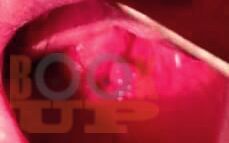

Гипертрофические состояния глотки

В настоящем учебном пособии для студентов, обучающихся по специальности Лечебное дело по дисциплине «Оториноларингология», в соответствии с программой по данной дисциплине систематизированы и последовательно представлены сведения о клинической анатомии и физиологии глотки; гипертрофических состояниях лимфаденоидного кольца Пирогова-Вальдейера и сопряженных с ними храпа и синдрома обструктивного апноэ сна. Знание этиологии, патогенеза, клинической картины, методов лечения необходимы в практике врача для клинической и дифференциальной диагностики.